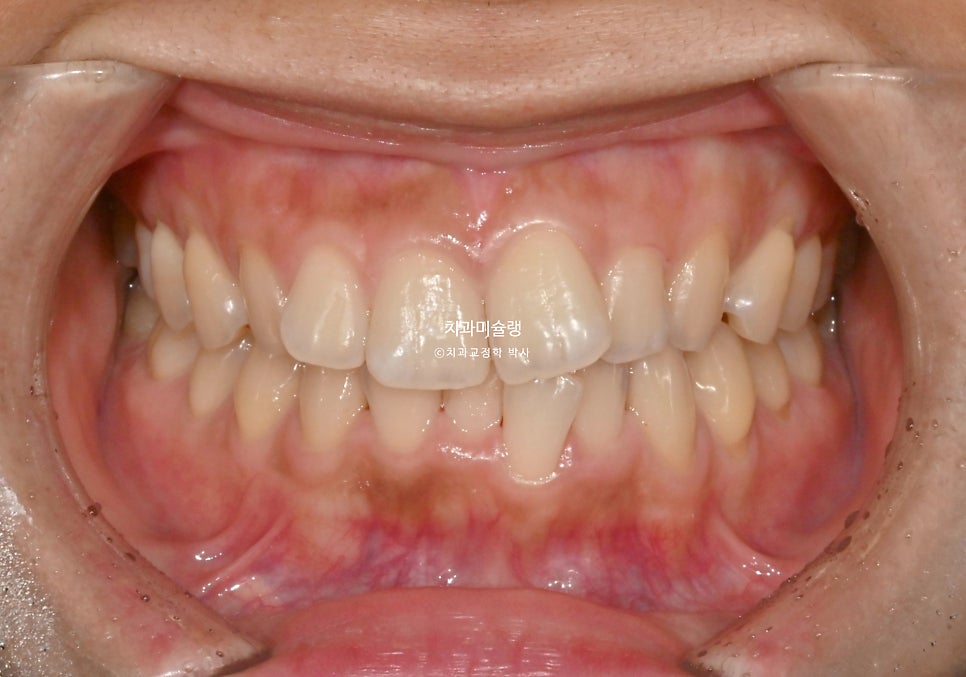

작년 여름, 교정치료를 위해 내원한 환자분 입니다.

앞니가 삐뚤하며 치축이 기울어져 있고 중심선이 약간 어긋나 있습니다.

그에비하면 어금니는 교합이나 배열이 좋은편입니다.

이정도 부정교합은 인비절라인라이트로 치료가 가능합니다. 완벽한 교합과 정렬을 위해 라이트 프로그램이 허용하는 14개의 장치면 충분하다는 이야기.